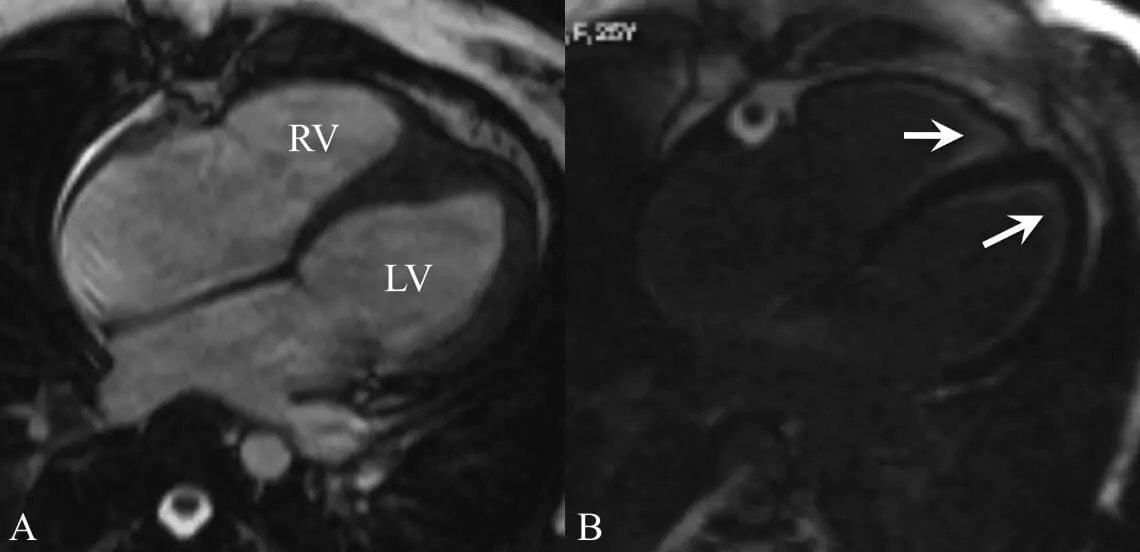

Cardiac MRI (Magnetic Resonance Imaging) is a sophisticated, non-invasive imaging technique that uses a powerful magnetic field to produce high-resolution images of the heart and major blood vessels - without any radiation. It provides detailed insights into:

- Heart muscle and wall motion

- Chamber size and function

- Blood flow patterns

- Inflammation and scarring (myocarditis, fibrosis)

- Congenital heart disease

- Cardiac tumours and pericardial diseases